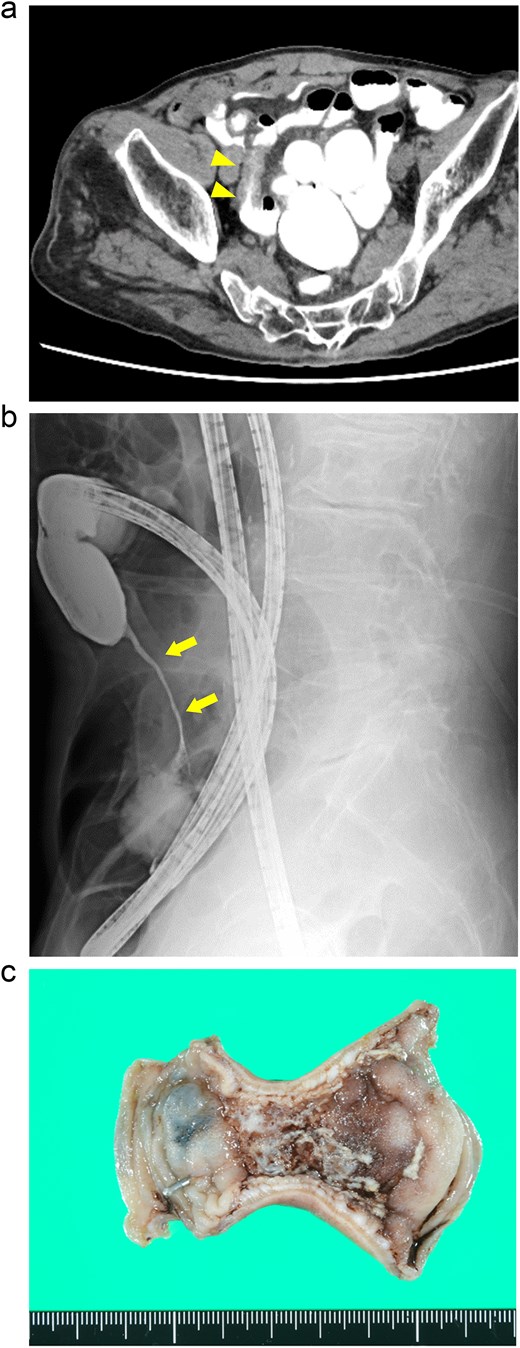

An 88-year-old woman presented with recurrent episodes of epigastric pain. Three months prior, she experienced similar abdominal pain, and CT revealed HPVG and mesenteric emphysema without mesenteric ischemia or bowel strictures. The patient’s symptoms resolved with conservative treatment, and none of the CT features remained by the follow-up. Her vital signs were stable, and most of the laboratory test results were normal, including WBC count (6700/μl), CRP concentration (0.95 mg/dl), Hb level (12.3 g/dl), and Lac concentration (0.9 mmol/L). However, her blood glucose level (BGL) was elevated (315 mg/dl), as was her glycated hemoglobin (HbA1c) level (9.0%). Contrast-enhanced CT revealed a segmental luminal stricture with wall thickening in the distal ileum, suggestive of bowel obstruction (Fig. 2a). A long intestinal tube was placed for luminal decompression, and fluoroscopy confirmed the presence of segmental, smooth luminal narrowing in the distal ileum (Fig. 2b).

Case 2: (a) Contrast-enhanced CT of the abdomen. The arrowheads indicate segmental luminal stricture with wall thickening in the distal ileum. (b) Fluoroscopy with a long intestinal tube. The arrows indicate a segmental, smooth luminal narrowing in the distal ileum. (c) Macroscopic view of the resected specimen. Circumferential ulceration and surrounding fibrosis are visible in line with the stenotic site.

Exploratory laparoscopy revealed an 8-cm-long bowel stricture with segmental induration 30 cm from the ileocecal valve, which was resected. The pathological specimen revealed circumferential ulcer formation at the stenotic site, accompanied by granulocyte infiltration and fibrosis extending from the submucosa through the proper muscle layer. No signs of tumors or IBD were noted (Fig. 2c). The postoperative course was uneventful, and she was discharged on the eighth postoperative day. By the 16-month follow-up, she had not had any recurrences of abdominal symptoms.